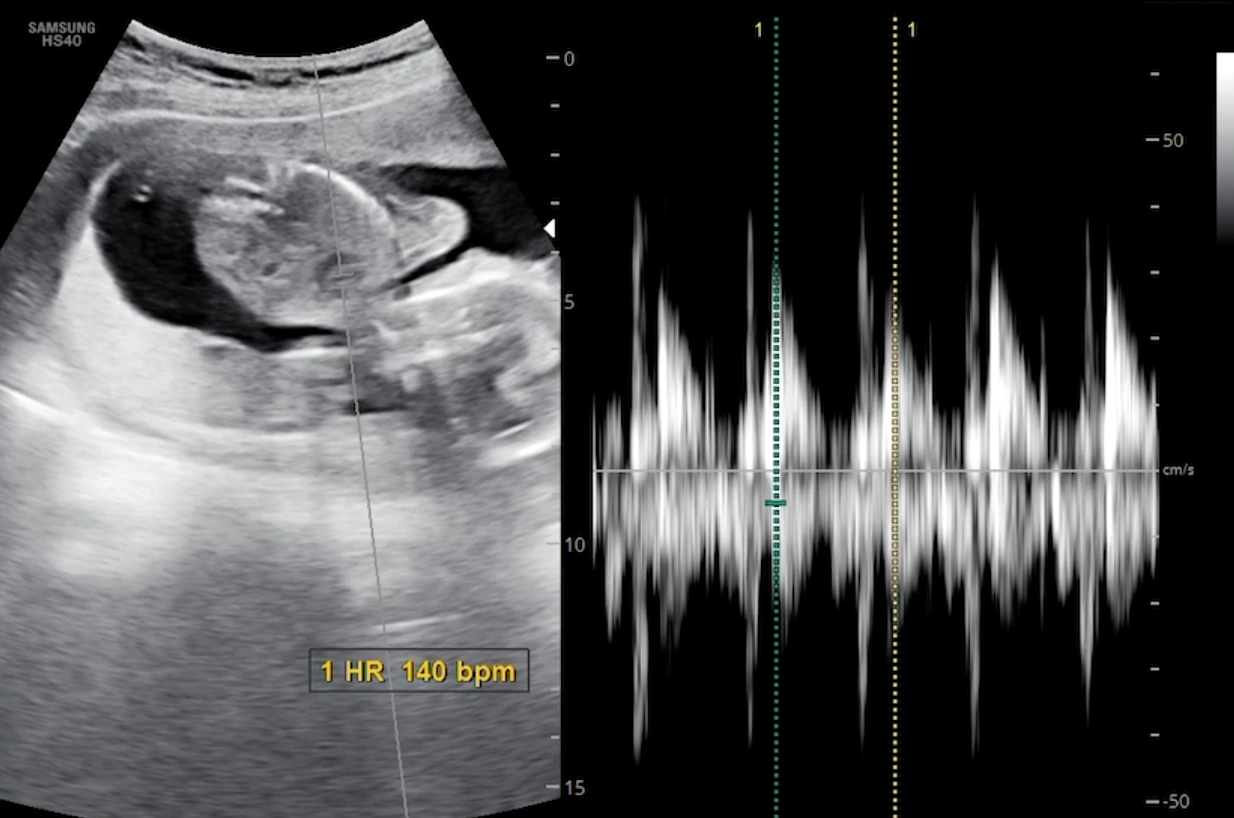

초음파는 정말 몇 분 안보고 금방 끝났구요. 21주 정밀초음파 때가 장기들을 세세히 보는 시기라고 하더라구요.

무무 심장 bpm은 140으로 정상범주라고 하셨어요 ㅎㅎ 처음에 심장소리 들을 때가 엊그제 같은데, 이제는 심장소리 듣는게 익숙해졌네요. 우렁차고 좋다~~